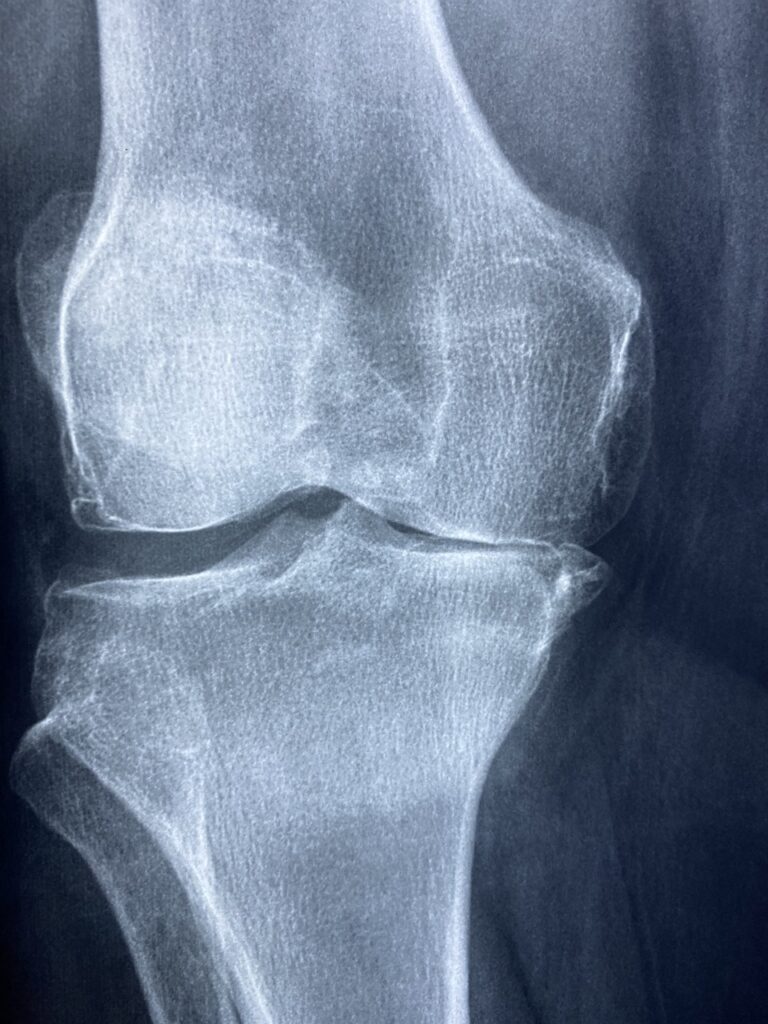

- Fractures and bone injuries

- Juvenile arthritis